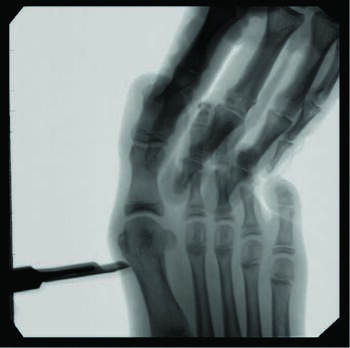

Documentation of surgical correction of hallux valgus first occurred in the early 1800s, with the earliest reports of percutaneous correction in the 1940s. Podiatric physicians experienced surgical restrictions at this time, and MIS provided an avenue for circumvention. Complications arose due to a lack of supportive means, and these outcomes led to an abrupt return to open procedures. The 1960s provided power equipment development and intraoperative fluoroscopy, which significantly improved outcomes of both open and percutaneous procedures. With the arrival of these modern tools, surgeons began to revisit the utilization of percutaneous procedures towards the end of the millennia. A subcapital osteotomy technique reported by Bosch, and “Simple, Effective, Rapid, Inexpensive,” modified by Giannini in the early 2000s, implemented a modern look at MIS hallux valgus procedures.8,9 Most recently, a guide to the percutaneous bunionectomy written by Siddiqui in 2014, and MIS radiographic outcomes in 2016, provided another available tool to surgeons, which decreased the complication rates and expanded the confidence in utilization of MIS bunion correction universally.10

One can allow early mobilization by immediate weight-bearing in the postoperative course, most notably providing a decrease in adhesions and consequent stiffness of the joint. Another advantage includes multiple viable fixation options, including splintage with a Steinmann pin through external fixation. Many long-term risks of internal fixation include foreign body reaction, growth disturbance, chronic infection, corrosion, implant migration, and potential interference in orthopedic treatment later in life.14 Schmittenbecher and coworkers described risks of implant removal in children with various fixation options, concluding that each patient’s treatment selection must weigh the benefits and risks.14 Steinmann pin fixation may, in my experience, alleviate these risks, removing it around four weeks postoperatively.

Some surgeons hypothesize that the lack of lateral capsular or tendon balancing procedures allows an increase in soft tissue tension to provide stability to the capital fragment of a construct that is not inherently stable. Common complications include relapse or malalignment, where the capital fragment achieves excess dorsiflexion or plantarflexion. The most common complication reported by some is pin site infection at 19.4 percent, successfully treated with oral antibiotics.10